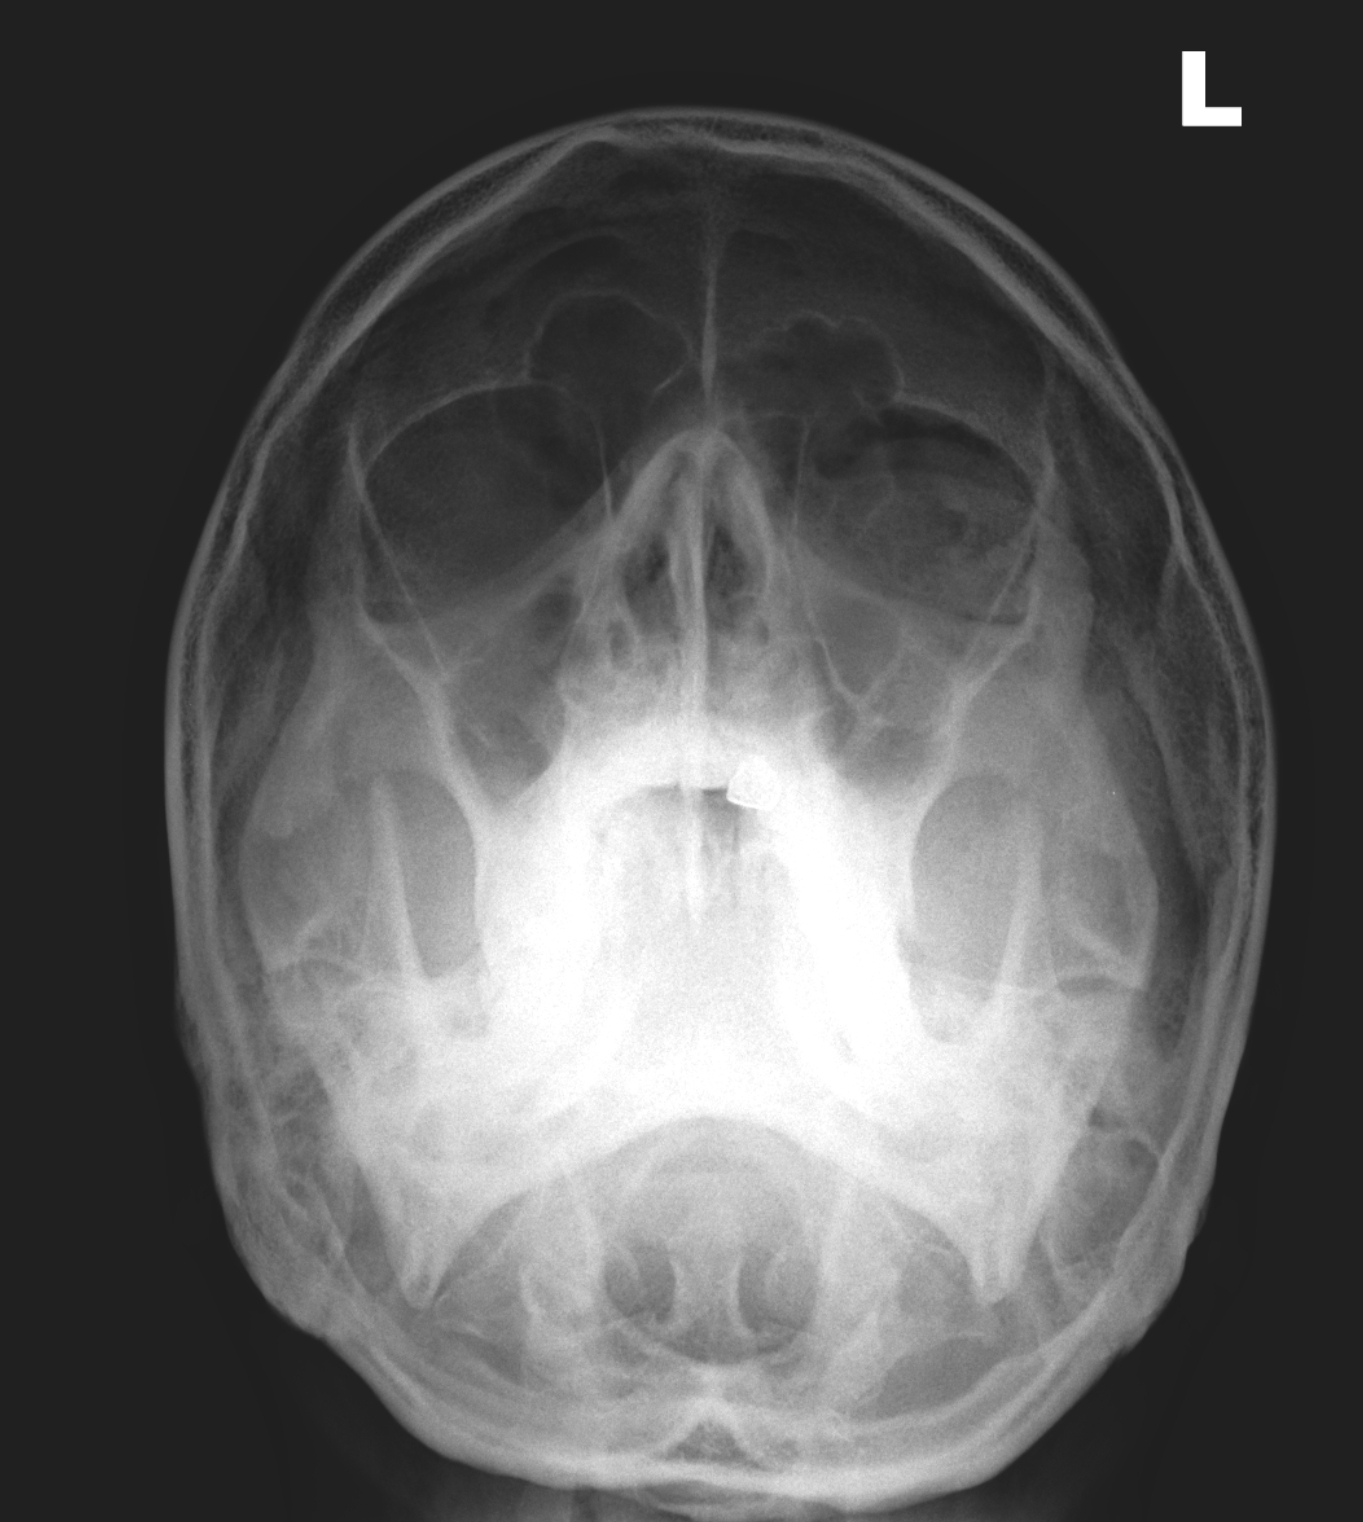

CASE 3

HISTORY

13 year old girl. Bilateral hip pain for 3-4 weeks. Difficulty in weight bearing.

QUESTION

Concentrate on the hip joints. Are both hips normal?

RADIOGRAPHS

ANSWER